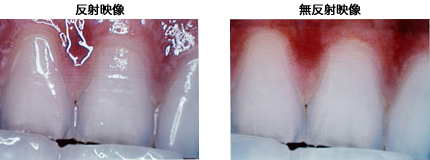

スカラ(株)は,世界で初めて内視鏡の「反射・無反射同時ライブ映像技術」の開発に成功した。今までの内視鏡は内蔵照明による対象物の「反射映像」のみを表示していた。本技術は「反射映像」に加えて,表面反射の無い「無反射映像」を同時にライブでモニターに表示することを可能にした。「反射映像」では表面反射映像を含むことで皮膚粘膜の凹凸形状も撮影でき,「無反射映像」では表面反射を完全に消去することで皮下の血管・色素の映像が鮮明に撮影できる。これによって内視鏡検査の鑑別の精度を向上させる期待が持てる。特許出願済。

同社では,皮膚がん診療の世界的権威である東京女子医科大学東医療センター皮膚科田中勝教授の指導の下,「反射」「無反射」映像を,手動切り替え式で撮影できるマイクロスコープを販売しており,皮膚がんの診断領域では10年以上にわたっての実績がある。皮膚がんにおいては,無反射映像の皮下の血管や色素分布を確認することが悪性診断の重要な目安となる。内視鏡においては手動切り替えでなく,例えば胃カメラにおいて,二つの映像を同時に観測することで「胃潰瘍」と「胃がんによる潰瘍」の鑑別などの精度があがることが期待される。